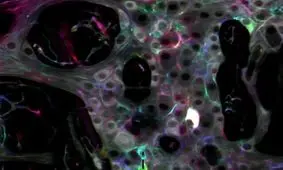

محققان موسسه فناوری کالیفرنیا (کلتک-Caltech) موفق شدند با استفاده از یک جعبه ابزار ژنتیکی، ذهن (سیستم عصبی) یک عروس…